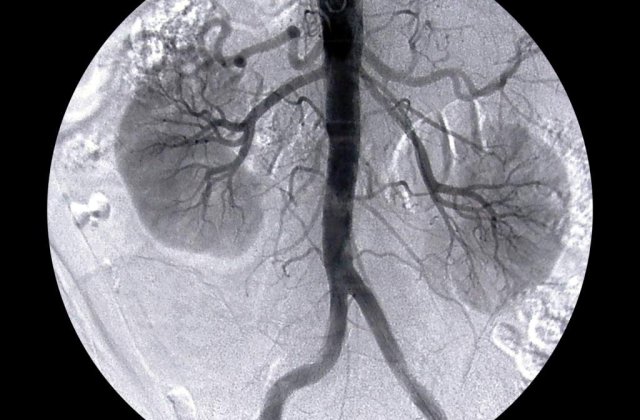

Potrivit unor surse medicale, unul dintre gemeni avea insuficienta renala si risca sa intre in blocaj. Pentru a nu fi trecut pe dializa, s-a luat decizia transplantului, acesta primind un rinichi de la fratele lui, geaman identic.

Fiind vorba de un transplant renal intre gemeni (donator - transplantat), a caror structura imunologica este de suta la suta, medicatia imunosupresoare nu mai este necesara, in acest caz riscul imunogic fiind zero.

Din iunie 1997 si pana in prezent, la Centrul de Chirurgie Urologica si Transplant Renal "Fundeni" a fost realizat un numar record de transplanturi, din care 80 la suta cu rinichi de la donatori in viata si 20 la suta cu rinichi de la donatori in moarte cerebrala, rezultatele fiind superioare multor centre de referinta din Europa, a precizat sursa citata.